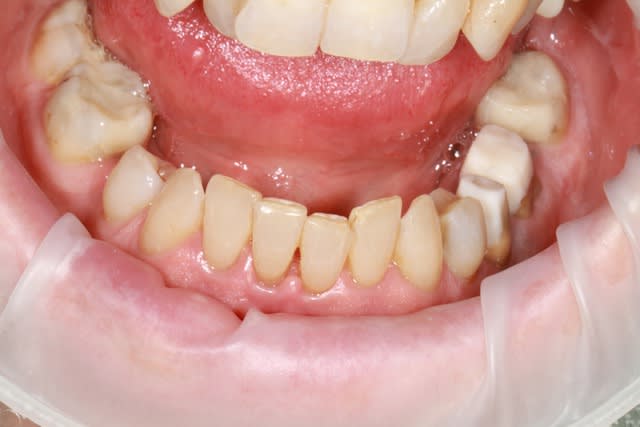

patiente 62 ans région Parisienne, appelle pour un avis, son praticien, paro, imlpanto etc... lui dit que sa paro n'a plus besoin de soin et propose pour les 6 antérieurs (j'ai le devis sous les yeux) 6 Inlay Core et 6 CCM...

Les panos sont du départ, les photos sont après un nettoyage ...profond et soins.

le problème de départ de cette patiente est paro...et bien sur l'ortho est une bonne idée, mais je ne pense pas que l'ortho permette de rétablir une DV correcte.

donc dans un premier temps détartrage, détartrage, détartrage Wax up, ....surfaçage couronne , amalgame à la benne taille des postérieurs inférieure et pose de provisoires pour valider la nouvelle DV.